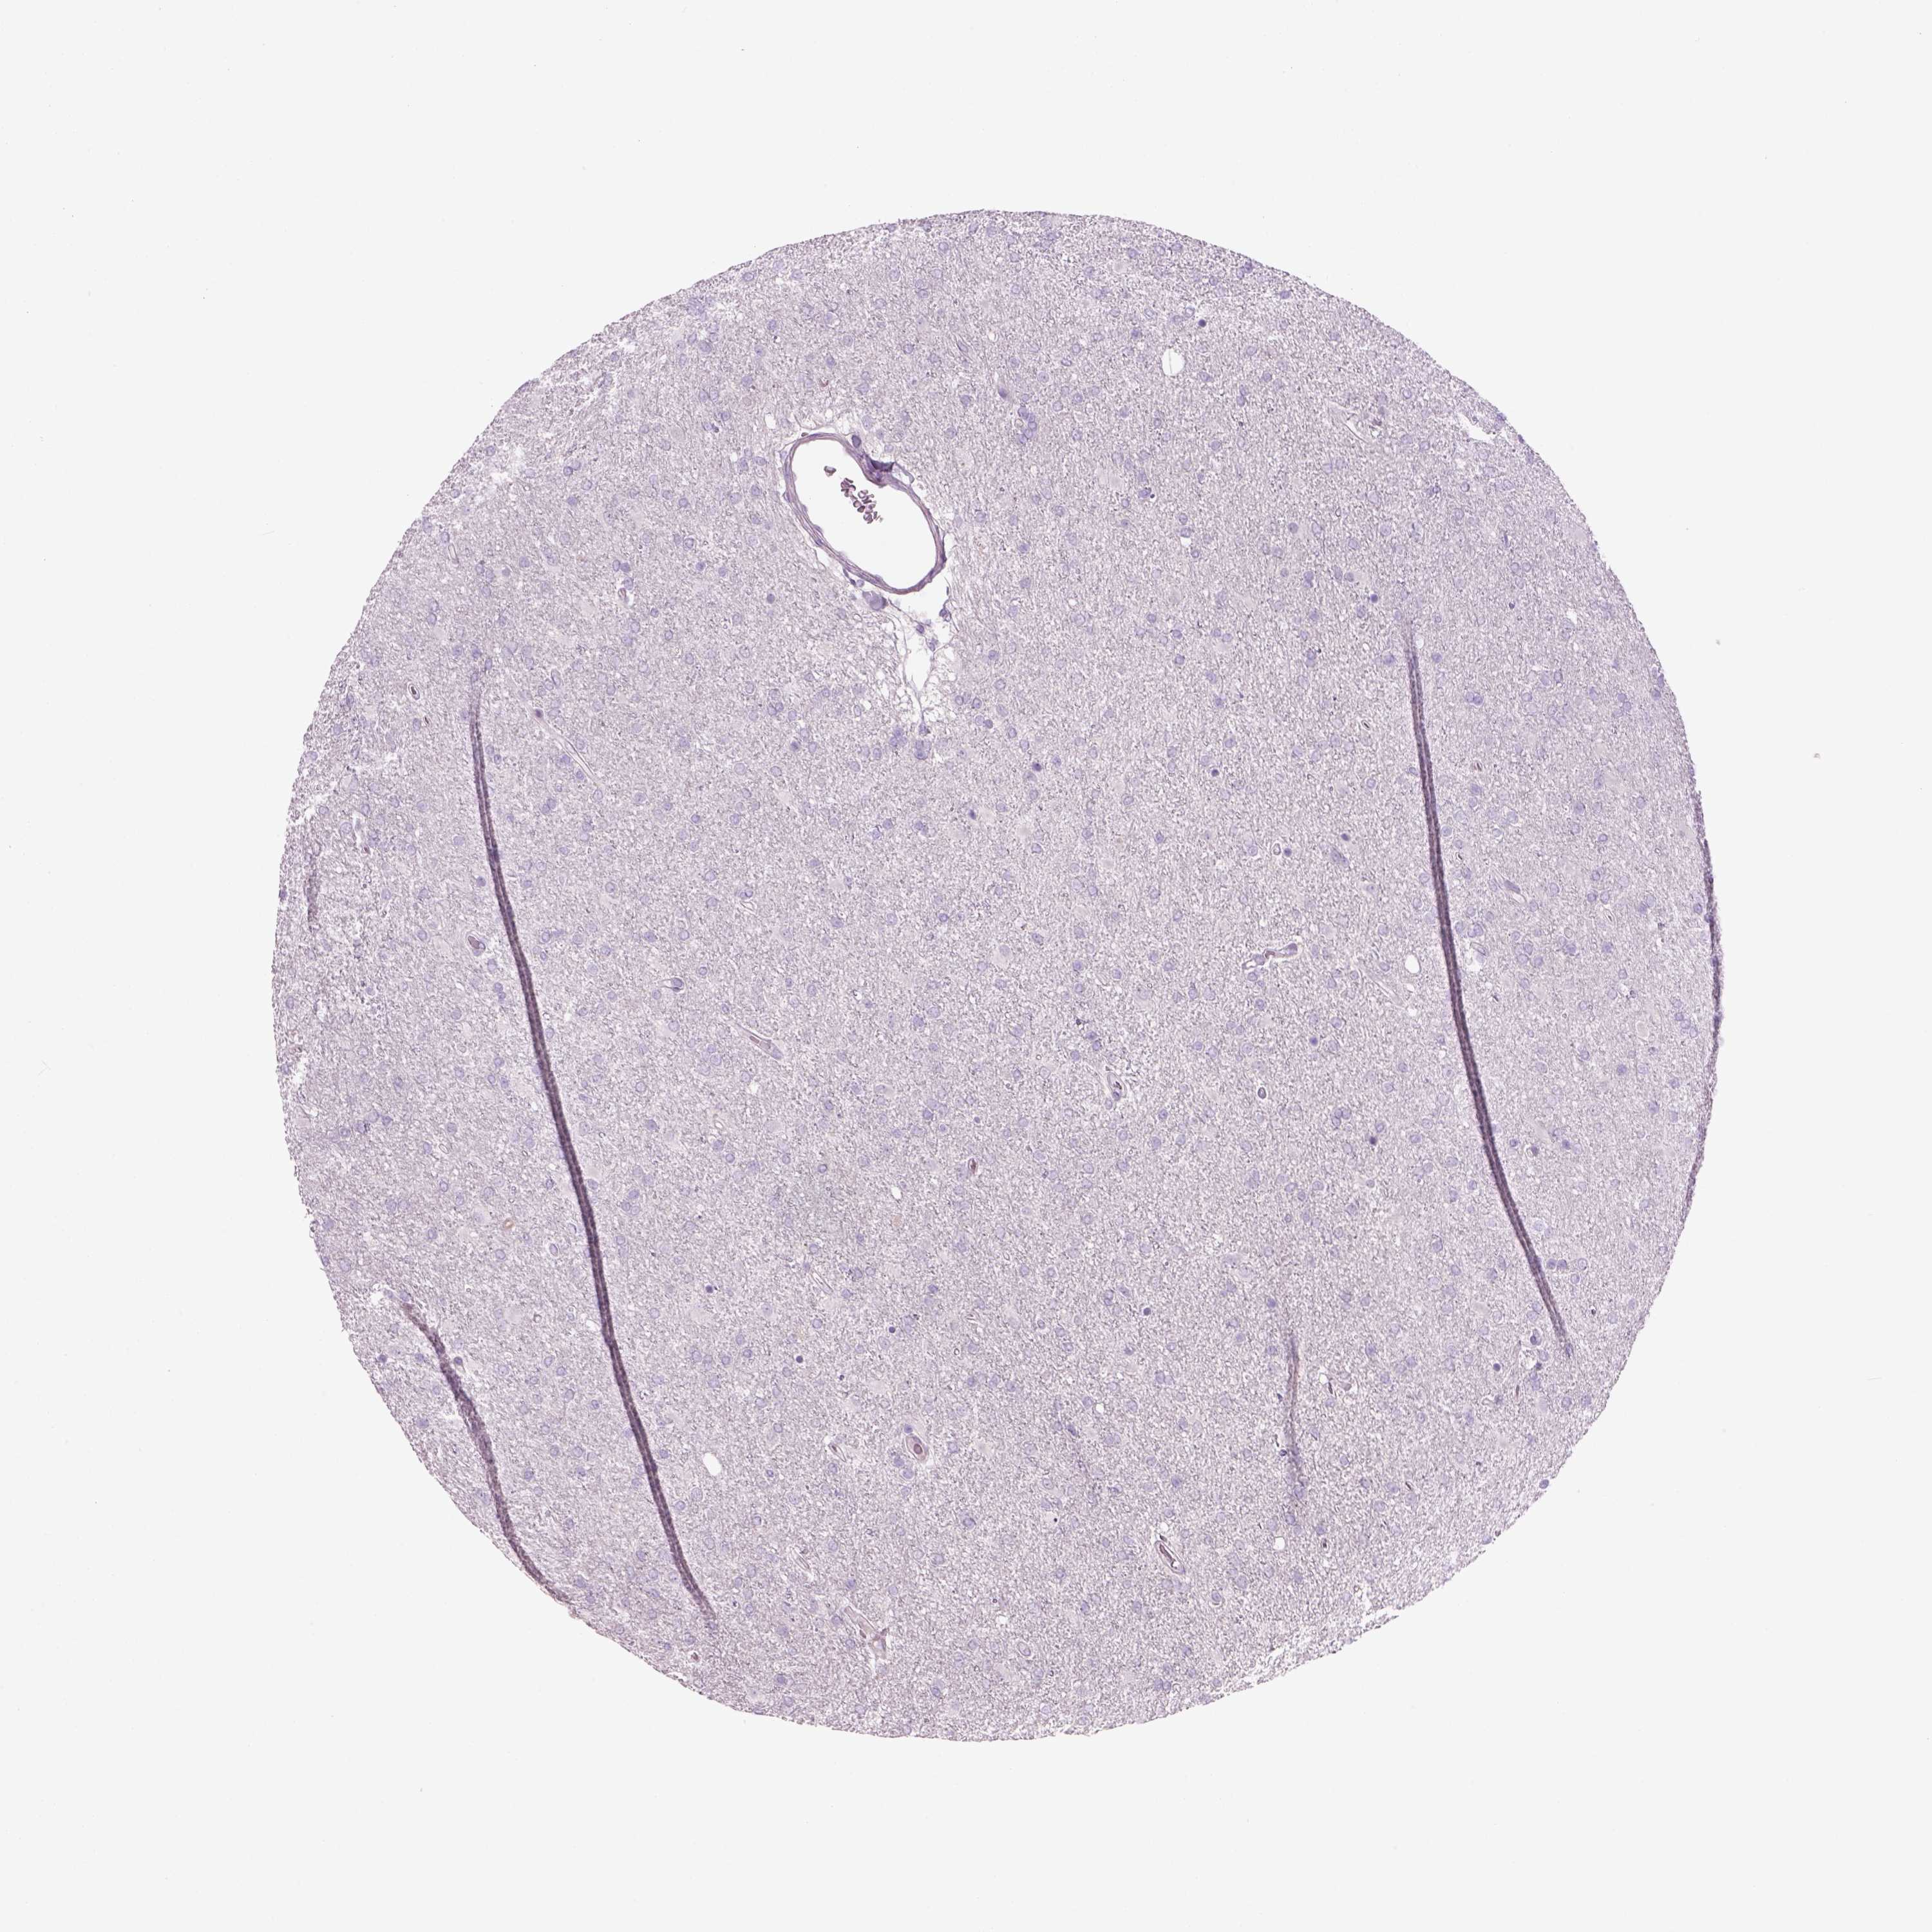

GLIOMA - Protein expressioni

A mouse-over function shows sample information and annotation data. Click on an image to view it in a full screen mode. Samples can be filtered based on level of antibody staining by selecting one or several of the following categories: high, medium, low and not detected. The assay and annotation is described here.

Note that samples used for immunohistochemistry by the Human Protein Atlas do not correspond to samples in the TCGA dataset.

Antibody stainingi

Antibody staining in the annotated cell types in the current human tissue is reported as not detected, low, medium, or high, based on conventional immunohistochemistry profiling in selected tissues. This score is based on the combination of the staining intensity and fraction of stained cells.

Each image is clickable and will lead to virtual microscopy that enables deeper exploration of all samples and also displays staining intensity scores, fraction scores and subcellular localization as well as patient and tissue information for each sample.

Antibody HPA073761

Staining

High

Medium

Low

Not detected

Intensity

Strong

Moderate

Weak

Negative

Quantity

>75%

75%-25%

<25%

None

Location

Nuclear

Cytoplasmic/membranous

Cytoplasmic/membranous,nuclear

Glioma, malignant, Low grade

Glioma, malignant, High grade

Glioma, malignant, NOS